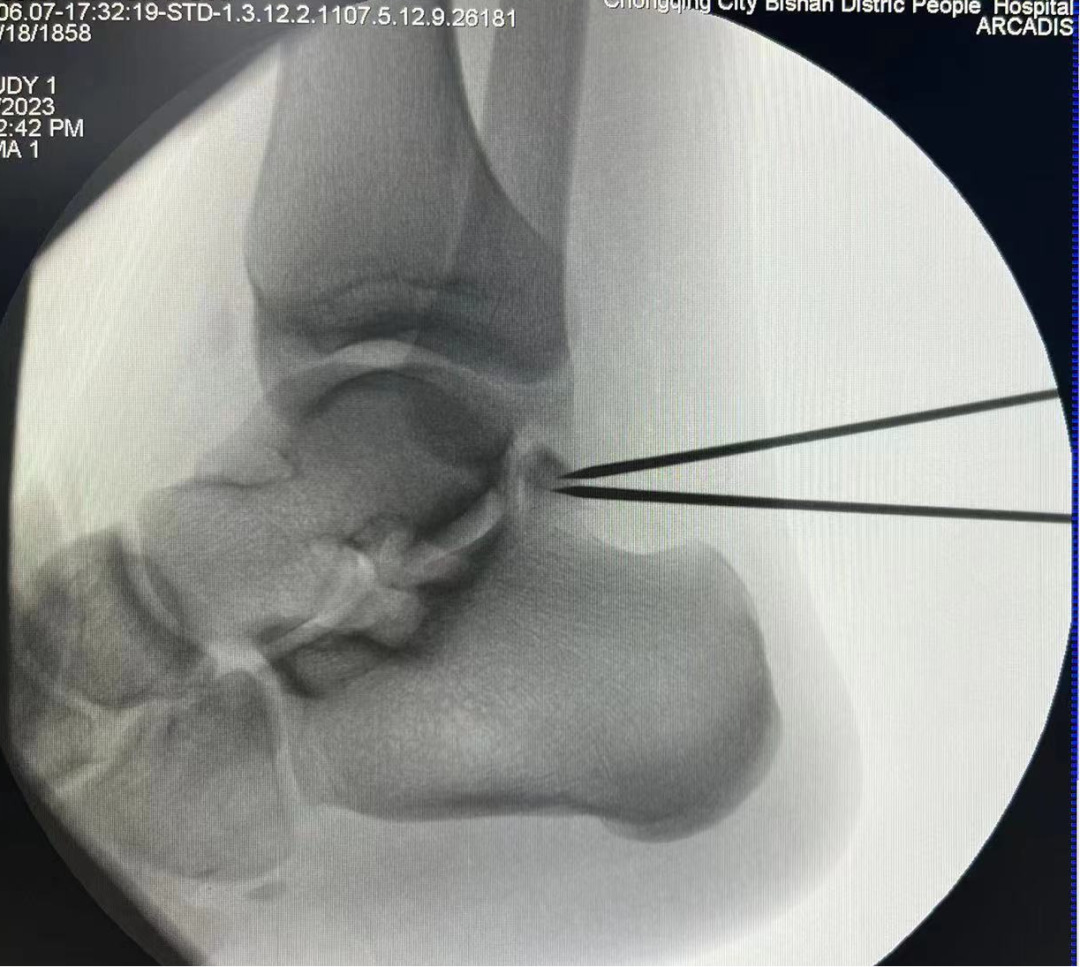

术中C臂定位病灶位置

踝关节镜下手术是一种微创治疗技术,其只有2-3个1cm左右的手术切口,在关节内镜直视下进行手术操作,可以对踝关节进行全方位检查,更直观地发现问题、解决问题。相较于传统手术,其具有创伤小、出血少、恢复快、美观等优点。

该手术的开展,标志着我院骨科在运动医学领域迈上了一个新台阶,实现了踝关节镜全内镜下手术从“0”到“1”的突破。